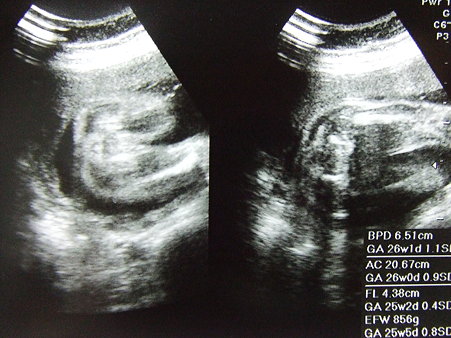

DSCF1164 posted by (C)Katze |

FL:4.83cm AC:20.67cm BPD:6.51cm お股が見えた。女の子らしい。 今日も心臓バクバク元気! 胃が圧迫。たくさん食べると吐く 便秘気味・昼寝 |